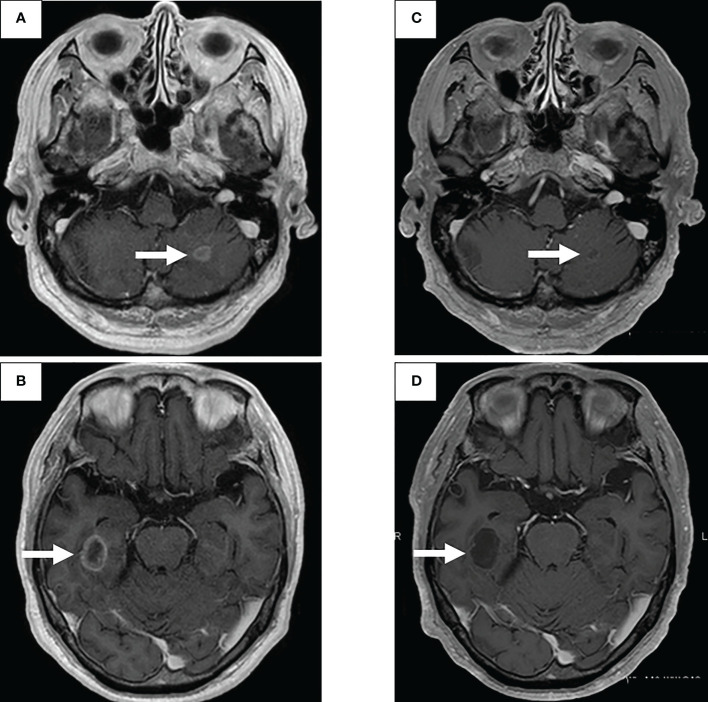

图1:在第一次就诊到开始进行第二次治疗期间,患者7年间原发病灶的顺序图像

一线治疗包括卡铂+培美曲塞+贝伐单抗,经过4个疗程后获得近乎完全缓解(CR),但鼻出血仍然持续,仅进行培美曲塞维持治疗。在维持治疗的25个疗程中实现了CR(图1C),但由于肾功能轻微恶化,治疗暂时中断。治疗结束后一年,CT显示原发病灶轻微进展(图1D),但复发速度较慢。确认CT复发一年后(图1E),重新开始培美曲塞单药治疗,原发病灶和淋巴结减小(图1F)。然而,在进行了32个维持治疗疗程后,出现了快速的全身进展。由于原发病灶再生(图1G)、对侧肺转移、多发性肝转移、右侧肾上腺转移和多发性脑转移(图2A、B),需要调整他的治疗方案。

通过支气管镜对原发病灶进行再活检,细胞学评估显示V级腺癌,组织学评估证实了这一结果。肿瘤精准用药850基因检测确认患者为RET融合基因阳性,随后于第二天给予240mg塞尔帕替尼。第13天的CT显示与基线影像相比(图1H),所有转移病灶,包括脑转移(图2C、D),均有良好的全身反应。由于2级肝酶升高,继续给予剂量减少的塞尔帕替尼(每天160mg)。使用高敏感度的下一代测序(NGS)面板系统:肺癌紧凑面板,并使用细胞学刷液进行RNA检测,证实了融合基因KIF5B外显子15;RET外显子12(K15RET12)。肿瘤精准药基因解码基因检测还能够从7年前的胸腔积液细胞块的福尔马林固定石蜡包埋(FFPE)标本中进一步确认RET(图3A、B),这些标本在恶性细胞的形态学上与再活检样本相似,具有大核仁(图3C、D)。从初始细胞块样本中收集到的RNA(1256ng)具有RNA整合数(RIN)值为4.8。单重PCR和NGS检测均检测到了K15RET12融合峰(图3)。